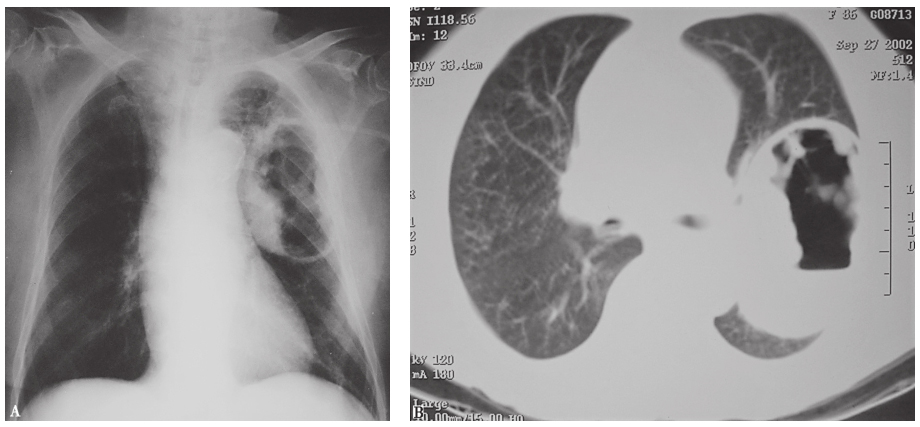

X线胸片(发病第10天):左下肺可见大片高密度影(图1)。

图1 发病第10天X线胸片表现

胸部CT(发病第14天):左肺下叶高密度影,边界欠清晰,其间可见多发囊性病变(图2)。

图2 发病第14天胸部CT表现